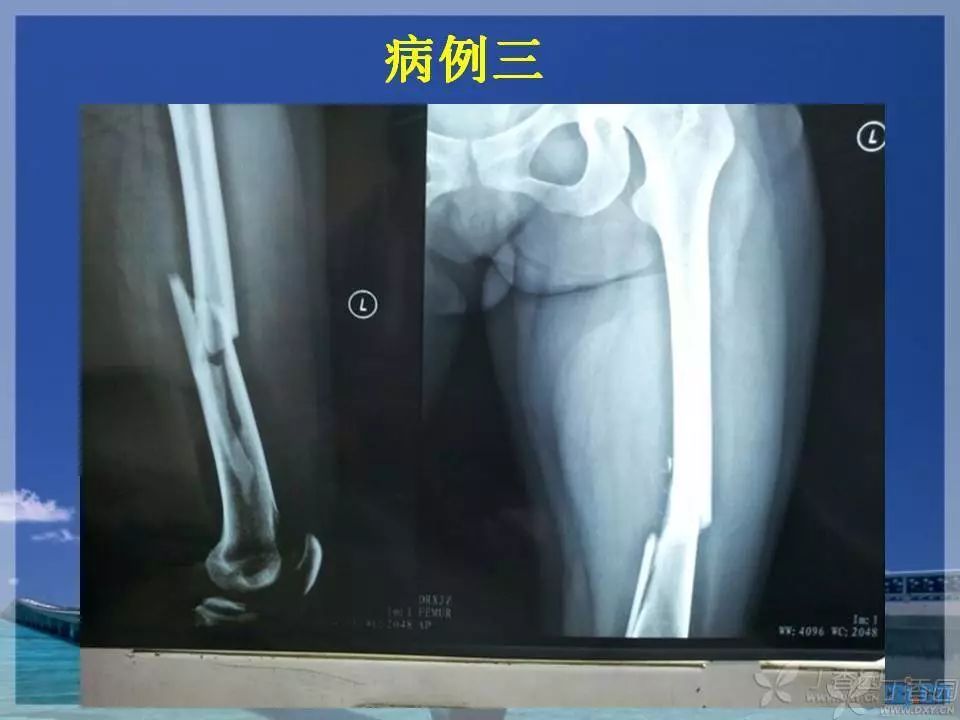

股骨干骨折是临床常见骨折之一,闭合复位髓内针固定治疗已成为首选。那么复位标准是怎样的?骨折块分离多少可以接受?钢丝可不可以用?不扩髓可以吗?相信看完下面这个课件你会有所收获~

1. ppt 中提到蝶形骨块移位大于 1cm 会影响股骨干骨折的愈合,这是一个台湾学者的观点,图中可以看见股骨内侧和后侧已经有骨痂生长,所以说 1cm 这个数据有待商榷。大于 1cm 的移位骨折愈合也不是什么问题。